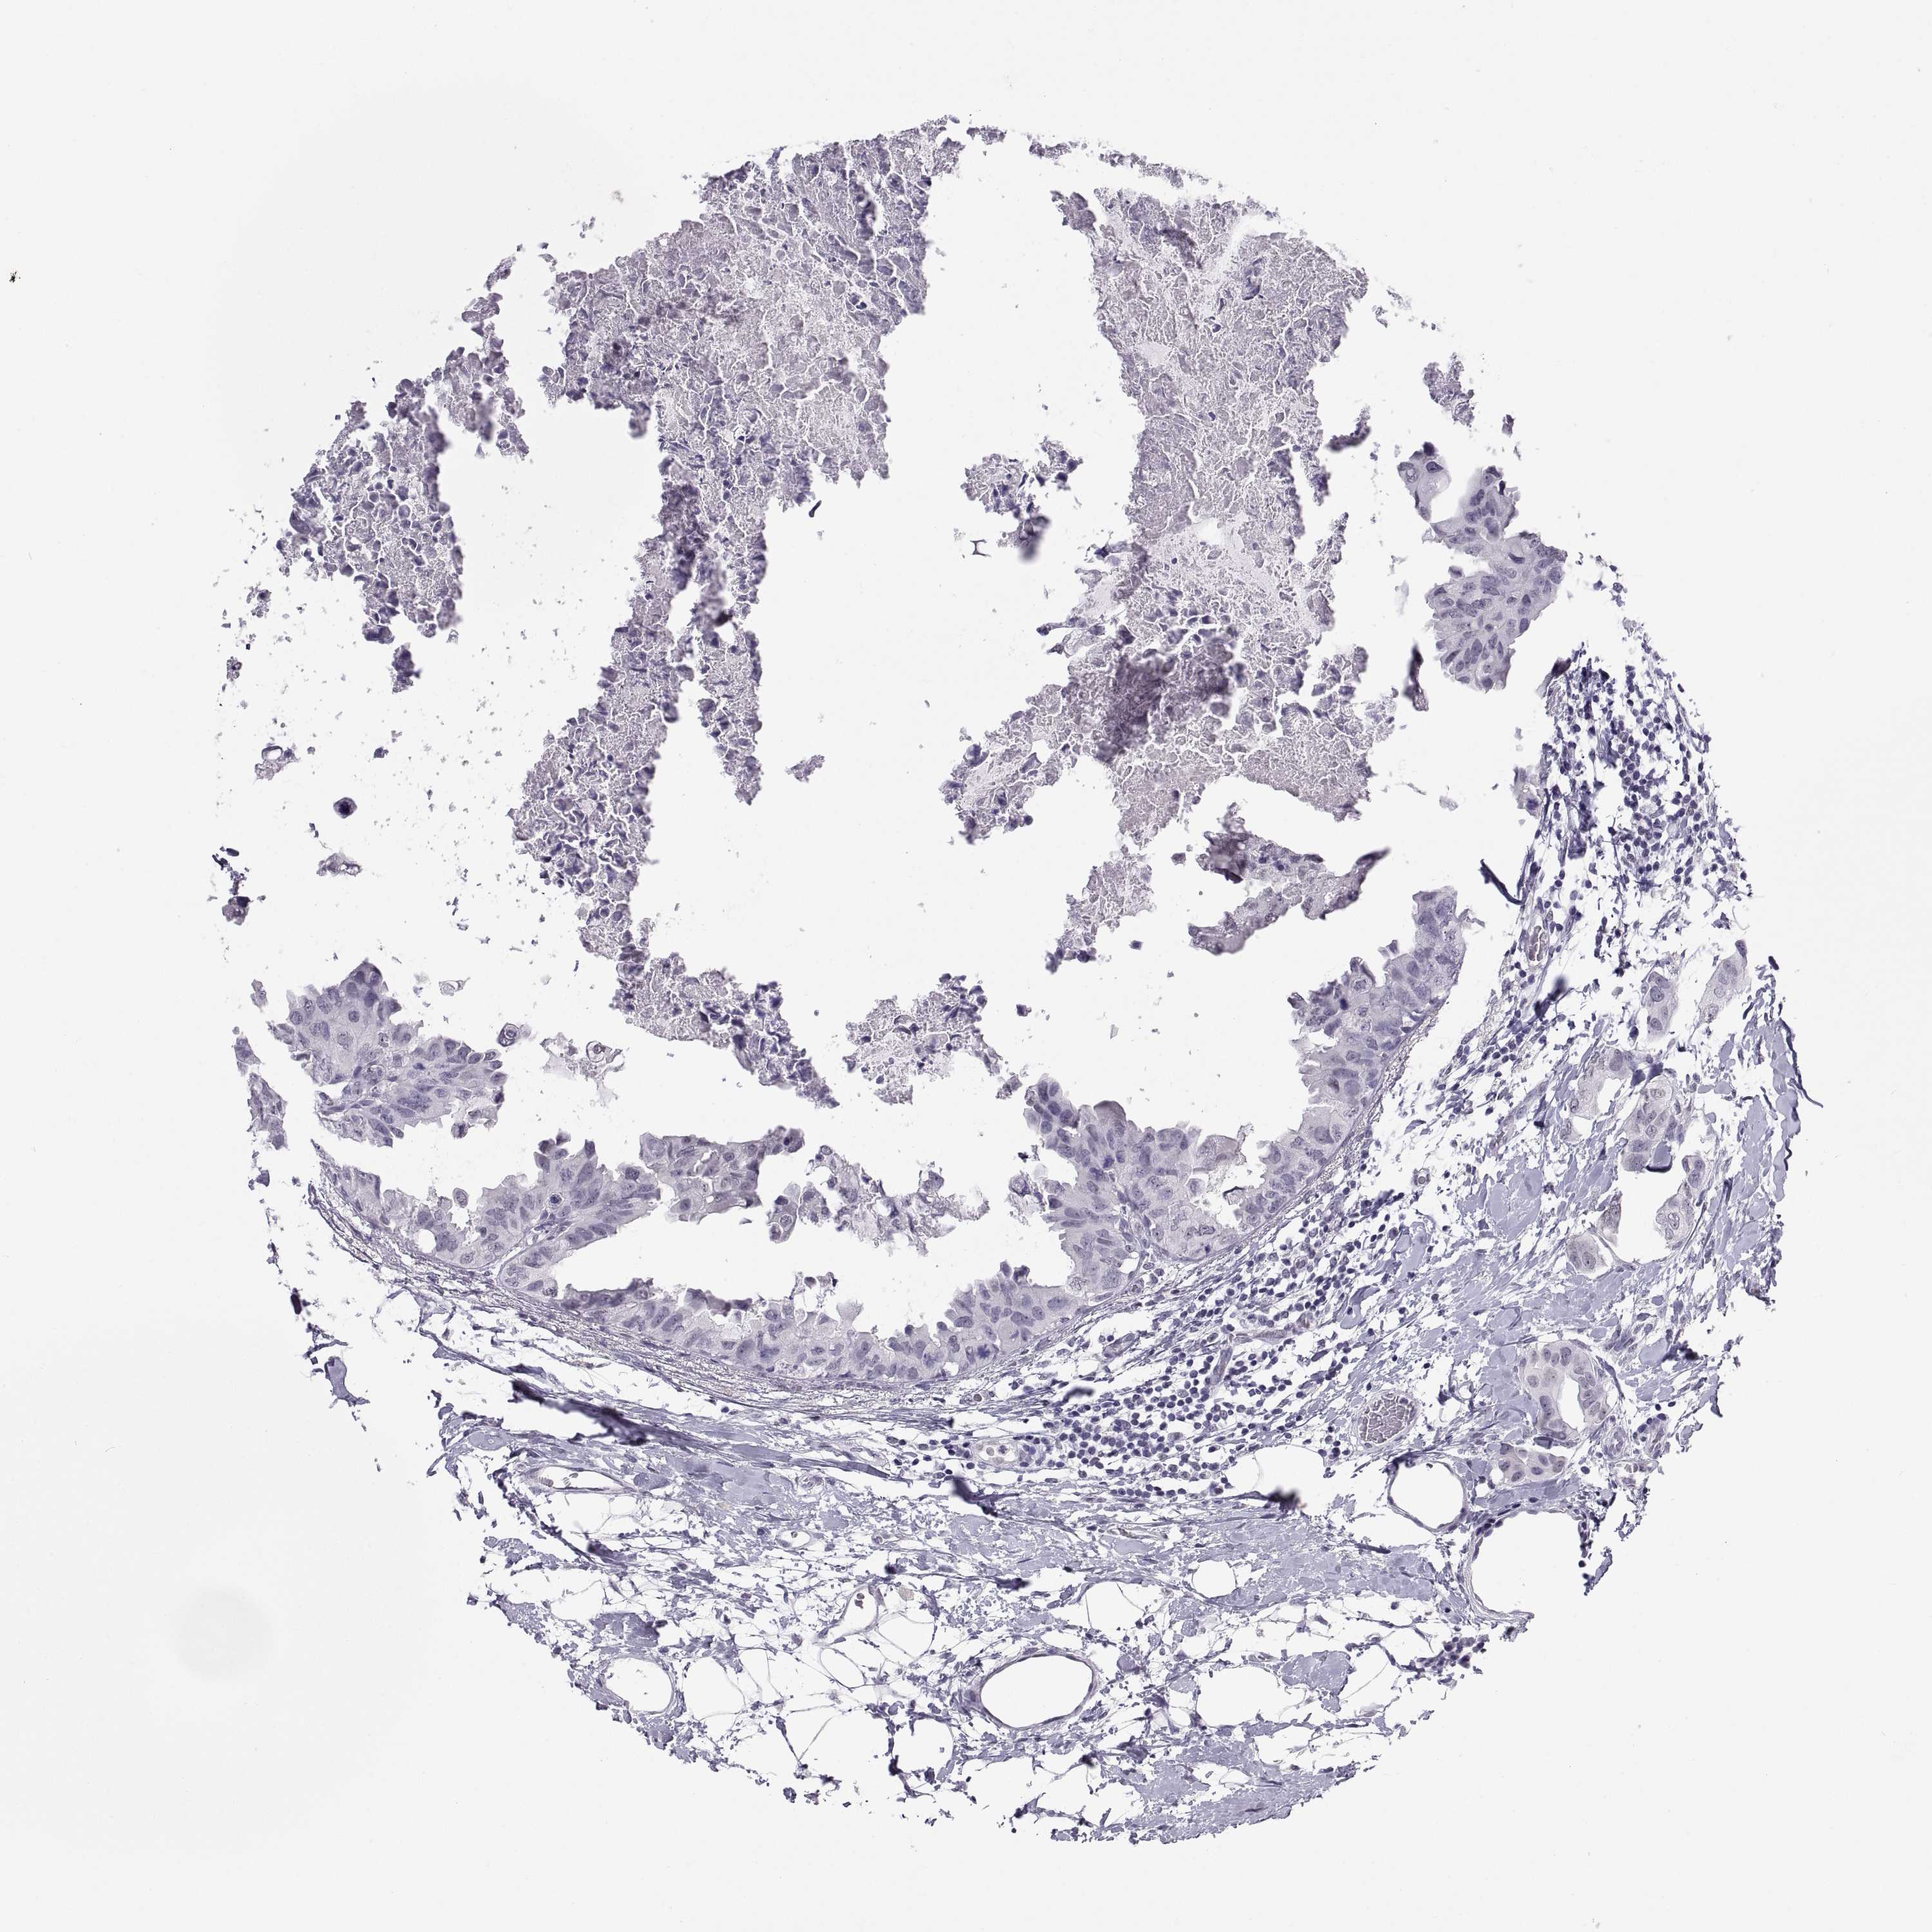

Breast cancer

Human cancer